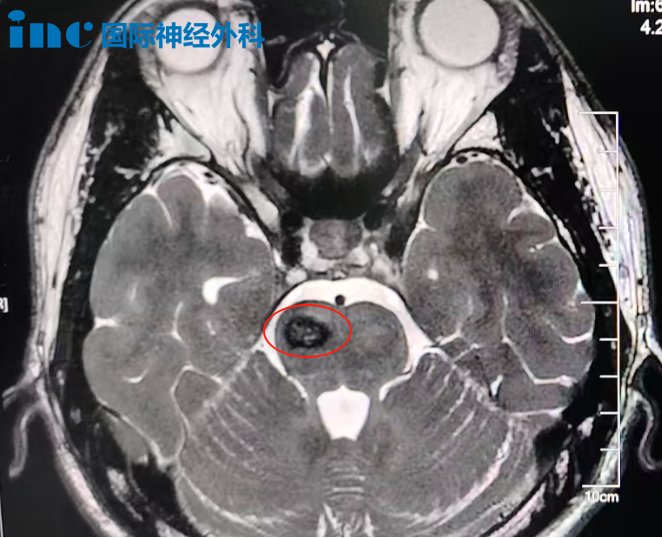

術(shù)前等候期間,陪伴文昊家人一同守候在手術(shù)室外的另一位脊髓髓內(nèi)腫瘤患者——43歲的周女士(T12 - L1髓內(nèi)占位)也順利完成手術(shù)。“一切都拜托教授了!”——這份沉甸甸的信任最終得到了圓滿回應(yīng)。

影像

在狹長(zhǎng)的走廊盡頭,巴教授遠(yuǎn)遠(yuǎn)望見周女士的家屬,未及走近便豎起大拇指——“一切順利,腫瘤全切!”這個(gè)手勢(shì)提前傳遞了手術(shù)成功的喜訊。